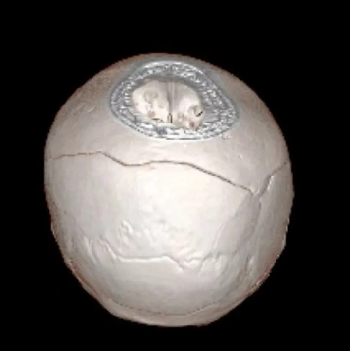

大骨瓣减压技术常用在重症颅脑损伤的救治,术后常遗留有颅骨缺损。传统的颅骨修复材料虽取材方便,但存在明显的排斥反应,而自体颅骨修补恰恰規避了这一缺点,成了颅骨修复的“金标准”。自体颅骨不存在常见的排斥反应,外形匹配、美观,真正做到完美“颅”初。

术后: